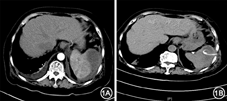

患者女,80岁。因发热3 d,腹泻1 d,收入我院感染和临床微生物科。入院体检:体温38.2℃,脉搏108次/min,呼吸20次/min,血压124/68 mmHg(1 mmHg=0.133 kPa)。咽部充血,双肺叩清音,双下肺可闻及散在细湿啰音。心率100次/min,心律不齐,各瓣膜区未闻及病理性杂音。上腹轻压痛(+)、右输尿管压痛点(+)。便常规:黄色软便,便红细胞(-)、白细胞(-)、潜血(-)。尿常规:尿红细胞(±),细菌计数85个/μl。血常规:白细胞19.82×109/L,中性0.94,血红蛋白117 g/L,血小板156×109/L,降钙素原(PCT)50.65 μg/L,C反应蛋白(CRP)138 mg/L。住院后经验给予阿莫西林-舒巴坦1.5 g,3次/d静脉点滴,抗感染治疗2 d后,最高体温仍达38.9 ℃,血常规:白细胞18.47×109/L,中性0.93,淋巴0.04;红细胞3.61×1012/L;血红蛋白103 g/L;血小板120×109/L;PCT 20.93 μg/L,考虑患者全身重度感染故将抗生素调整为哌拉西林-他唑巴坦4.5 g,每8小时1次。患者既往有心房颤动病史30年,高血压10年,最高血压180/130 mmHg,糖尿病病史10年。入院后胸部CT提示:双肺条索及磨玻璃密度影,考虑间质性改变合并轻度炎症,双侧胸膜局限性增厚、粘连,双侧胸膜腔积液;脾脏低密度灶,建议腹部进一步检查。入院后第4天全腹增强CT显示脾内囊性占位(图1A),考虑脾脓肿可能性大。行脾脓肿穿刺引流术,引流约100 ml褐色浑浊液体,引流液常规:李凡他试验++;细胞总数16 243 537个/μl,白细胞数963 537个/μl,分类单个核细胞5.00%;引流液生化:总蛋白13.20 g/L;氯98.7 mmol/L;糖14.88 mmol/L;乳酸脱氢酶5 314 U/L;腺苷脱氨酶509 U/L。查患者白细胞计数及PCT均呈下降趋势,继续哌拉西林-他唑巴坦抗感染治疗,入院后第7天患者体温恢复正常,引流管通畅,每日可有10 ml左右黄褐色脓液引出,患者病情好转。入院第11天,无发热,PCT 0.30 μg/L较前显著降低。入院14 d后,复查腹部CT脾内囊性占位明显缩小(图1B)。继续抗感染治疗6 d后,PCT 0.05 μg/L,患者病情稳定出院。